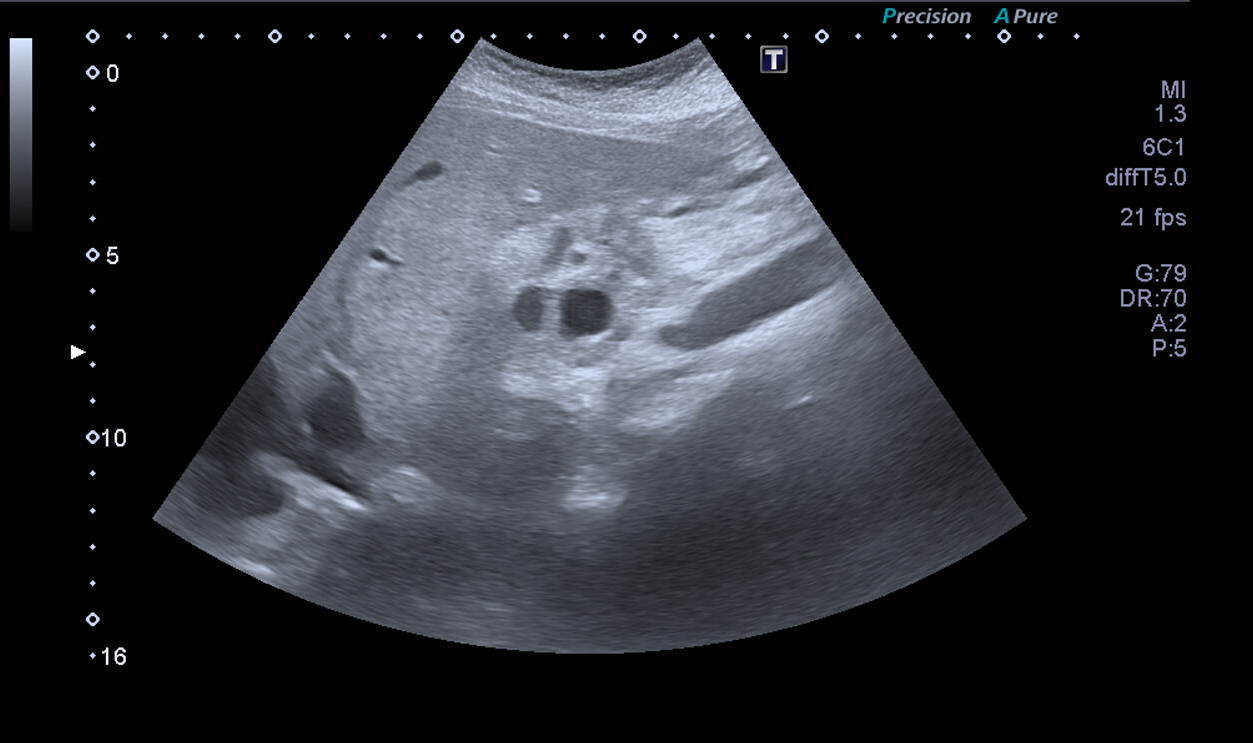

Ante la situación de dolor abdominal hacemos ecografía a pie de cama: se evidencia imagen redondeada de contenido heterogéneo de aproximadamente 38 mm, con dos imágenes redondas anecoicas en su interior en cabeza de páncreas. Restos de la exploración ecográfica sin alteraciones.

Juicio Clínico: Imagen redondeada de contenido heterogéneo de aproximadamente 38 mm.